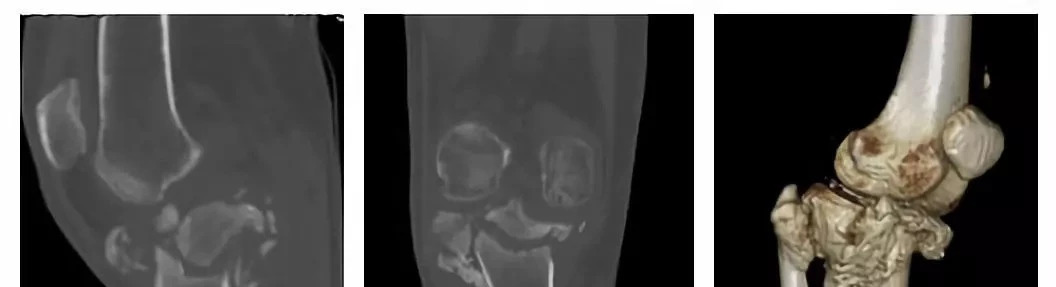

膝关节术前CT片

陈先生抱着一丝希望找到了骨科主任关振鹏教授并入住病房。入院检查显示陈先生有严重的下肢畸形,膝关节肿大、积液,双下肢乏力,膝周痛觉缺失,关节活动障碍,情况非常复杂。影像学提示膝关节对位不良,关节半脱位,关节间隙不规则,胫骨上段干骺端结构紊乱、胫骨平台大面积塌陷,呈现陈旧性粉碎骨折表现,局部骨缺损严重。在仔细分析陈先生的病情后,关主任鼓励陈先生要重燃战胜疾病的信心,准备为他实施人工膝关节置换手术,帮助他重新站起来!